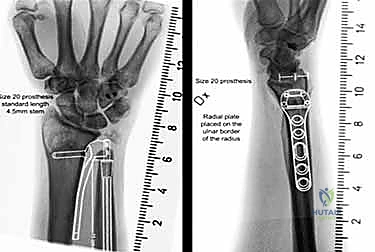

4. اختيار وتجربة المفصل الصناعي (Sizing and Trialing)

هذه خطوة حاسمة. يقوم الدكتور هطيف بوضع نماذج تجريبية (Trials) للمفصل الصناعي بأحجام مختلفة. يتم اختبار حركة الساعد (الكب والاستلقاء) للتأكد من السلاسة، والاستقرار، وعدم وجود أي احتكاك، والتأكد من استعادة الطول الصحيح للزند.

5. زراعة المفصل النهائي

بعد تحديد الحجم المثالي، يتم إدخال المفصل الصناعي النهائي. تتكون معظم المفاصل الحديثة من جذع معدني (غالبًا من التيتانيوم) ورأس أملس (قد يكون معدنيًا أو من السيراميك أو البايروكربون). يتم تثبيت الجذع داخل العظم إما بالضغط (Press-fit) أو باستخدام الأسمنت العظمي، حسب جودة عظام المريض.

3. التصوير المقطعي المحوسب (CT Scan)

يوفر التصوير المقطعي رؤية ثلاثية الأبعاد مفصلة للغاية للعظام. إنه ضروري لتقييم شكل الشق السيني في الكعبرة، وتحديد مدى التآكل، والتخطيط الجراحي الدقيق لاختيار حجم ونوع المفصل الصناعي المناسب.